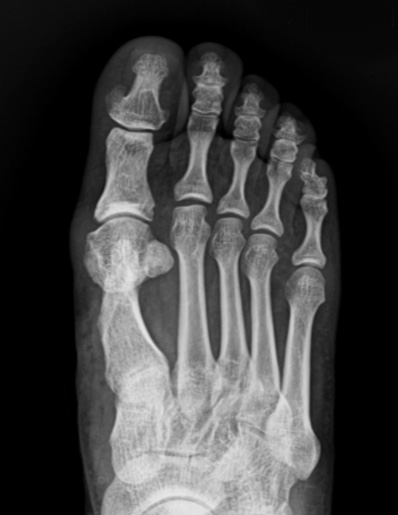

수술 전

수술 후

기구제거 후

* 환자에게 받은 소중한 자료입니다.